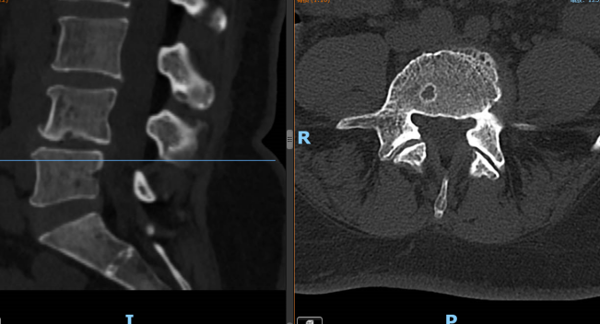

▲③术前CT片

“医生,我这半年来腰痛的厉害,右腿现在又痛又麻,走路都困难,有什么办法处理吗?”在骨科诊室,患者谭阿姨(化名)苦恼地说道。捆绑调教 骨科脊柱外科专业专家欧裕福副主任医师详细询问谭阿姨病史,并为她安排了细致的检查,最终诊断为腰椎管狭窄症+腰椎滑脱症。

结合谭阿姨下腰部明显压痛、右下肢疼痛及活动障碍等症状,骨科脊柱外科团队经过多次术前讨论,并联合麻醉手术中心团队,为谭阿姨制定了个性化的诊疗方案,决定运用经皮内镜下腰椎减压融合技术为患者进行治疗。